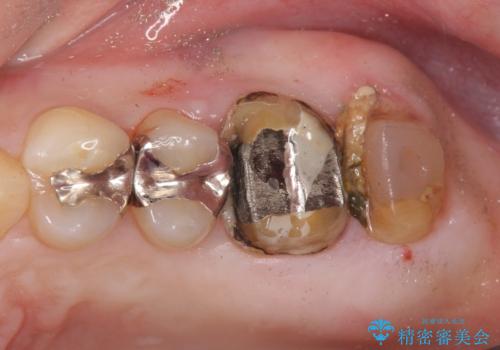

- 銀歯をやりかえたいが他院で抜歯と言われセカンドオピニオンで来院。適合の悪い被せ物が入っており、まずは古い材料、虫歯をとり保存可能か確かめる必要があり、拡大鏡下で全て取り除いたら歯質が歯茎の中まで虫歯がありました。このまま無理やり型取りをして被せ物を作っても不適合な被せ物が入る可能性が高いため歯茎を切り取る手術(ディスタルウェッジ)を行いました。そして再根管治療を行いゴールドの被せ物で治療を行いました。